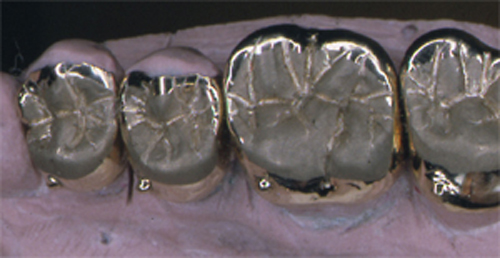

INTRODUCCION La rehabilitación oral como especialidad multidisciplinaria, obliga al profesional a pensar en términos complejos, donde la observación de todos y cada uno de los elementos constituyentes del sistema Estomatognático se hace imprescindible para el arribo a un diagnóstico de certeza. Sabido es que el esmalte dentario se desgasta con el correr de los años. Sin embargo, es importante determinar como se produce dicho desgaste y si éste responde a una cuestión de carácter fisiológico o se trata de una manifestación patológica. Adaptativas Tienen paca velocidad de desgaste. Su localización es exclusivamente de esmalte. No hay deformación oclusal y se producen cuando el sistema neuromuscular es aún inmaduro. Madurativas En la oclusión adulta los contactos interoclusales son puntiformes, ya que contactan convexidades contra convexidades. Parafuncionales Son las únicas que podemos considerar patológicas. Su velocidad de desgaste es mucho mayor y se localizan en dentina, pudiendo o no ser sintomáticas. En los anteriores el desgaste puede ser plano y parejo, lo que significa que el paciente bruxa en sentido anteroposterior. Si por el contrario, el desgaste es curvo, el bruxismo es de carácter latero-lateral. En los posteriores podemos observar en casos avanzados que las cúspides estampadoras presentan una facetamiento mayor que las cúspides de corte, ya que en las lateralidades aquéllos que rozan el doble de veces que éstas últimas, dando lugar al llamado desgaste “en olla” e invirtiendo la curva de Wilson. MATERIAL Y MÉTODOS En el desarrollo de este trabajo se utilizaron onlays de oro (Ventura 120). CASO CLÍNICO El paciente se presenta a la consulta derivado y con severas mialgias difusas y referidas fundamentalmente a la cara, región posterior del cuello y ocasionalmente en la región occipital y temporal. Mujer 55 años, prácticamente sin historia odontológica anterior, ya que dice tener una dentadura excelente y que sólo visita a su dentista con relativa periodicidad para limpiezas, ya que caries cree no tener. Se evidencian signos depresivos cuando manifiesta que no sabe como dar solución a su problema. El examen periodontal denota bolsas poco profundas salvo en el incisivo superior lateral izquierdo, que también ofrece una moderada movilidad y ligeramente vestibulizado. El examen de la ATM determina la presencia de ruidos articulares en apertura y cierre y dolor a la palpación. Durante este examen manifiesta haber tenido dificultades para la apertura en reiteradas ocasiones. Fig 1/2 Se toman modelos de estudio y se duplican. Antes de proceder a su correspondiente montaje en un articulador semiajustable, se observan individualmente cada uno de3 ellos haciéndose ya objetiva la presencia de facetas de desgaste que, sin duda, tienen un origen y que nos darán la clave de nuestro diagnóstico (Fig. 3). Montados ya los modelos en oclusión en relación céntrica, mediante el que considero el más fisiológico medio de obtención de la misma: las laminillas de Long, preconizado por el Dr. W.H. McHorris (*), y que nos permite romper con los engramas o patrones de memoria muscular que trae el paciente y que en muchos casos, como éste, llevan a la mandíbula fuera de su posición esqueletal fisiológica, y que la obliga a trabajar en medio de contracturas musculares fundamentalmente del pterigoideo Externo. Cabe en este punto recalcar que es la ORC la única posición diagnóstica posible, la que, además de permitirnos obtener el eje de bisagra Terminal, es la única posición repetible. Al mirar los modelos montados según estos conceptos, podemos ver un punto prematuro de contacto (contacto único) (Fig. 4) Llevamos entonces la rama inferior de nuestro articulador hacia la posición a que dicho punto la guía, alcanzando la oclusión habitual (OH) en la que el paciente desarrolla su masticación. Podemos ver entonces la migración que dicho maxilar realiza hacia delante y a la izquierda, produciéndose una discrepancia horizontal. Dicha discrepancia obliga a la permanente contractura del pterigoideo externo del lado opuesto y el consecuente encadenamiento de pequeñas contracturas entre los músculos protagonistas, antagonistas y agonistas que rigen el movimiento. Procedemos a realizar el ajuste oclusal en el articulador mediante sustracción y adición, anotando prolijamente la secuencia del mismo, obteniendo así un único arco de cierre: ARCO DE CIERRE TERMINAL DE BISAGRA; y logrando mediante composites en las desgastadas puntas caninas, una disclusión canina (oclusión mutuamente protegida). Transferimos nuestro primer desgaste a la boca e instalamos la placa. Una semana después de uso nocturno pedimos al paciente que regrese, permaneciendo la placa en posición desde unas horas antes de la consulta, y observamos la enorme destalación que experimenta la mandíbula. Hacemos entonces un nuevo ajuste de la oclusión en boca. Adicionamos más composite a los caninos, tal como antes lo habíamos hecho con cera en el articulador. En este punto del proceso, vinculando ya la sintomatología con la discrepancia, evaluamos si la estabilidad oclusal será permanente o no. Al observar que los contactos son de superficie contra superficie, donde las fuerzas de deslizamiento se transforman en fuerzas de rozamiento (factor de alto potencial patológico) decidimos reestructurar la morfología oclusal para finalmente obtener los cuatro pilares fundamentales de la oclusión orgánica: AXIALIDAD, ESTABILIDAD, NO INTERFERENCIA, Y ALINEACIÓN TRIDIMENSIONAL. Considerando la edad de la paciente, sus escasas exigencias estéticas y el valor otorgado por la misma a la recuperación ad integrum de sus funciones, optamos por el oro como material óptimo de elección. Procedemos entonces a realizar sobre nuevos modelos de trabajo, con guía anterior ya modificada, un encerado de las tablas oclusales premolar-molar mediante el método de encerado progresivo de Meter K. Thomas. Obtenemos réplicas en yeso de este encerado y lo estampamos obteniendo así una matriz que reproduce las caras oclusales previamente diseñadas, este estampado luego nos servirá para obtener un juego de provisionales de metacrilato, según nuestra primera concepción de la morfología oclusal necesaria para obtener Estabilidad y Alineación Tridimensional, ya que los otros dos pilares fueron obtenidos: Axialidad al obtener un único arco de cierre, y No Interferencia con la modificación de la guía anterior. (Fig. 5/6). Construimos los provisionales a partir del estampado, lubricando previamente los muñones con una crema de corticoides para contrarrestar los efectos inflamatorios del metacrilato, y los cementamos con un producto a base de hidróxido de calcio, previa comprobación en el articulador de que se cumplen con los mismos todos los conceptos proyectados. En las siguientes dos semanas , durante las cuales la paciente sigue durmiendo con la placa de relajación colocada, seguimos ajustando la oclusión observando que la mandíbula prosigue aún más su distalación. Esperamos el período de tiempo necesario para que se estabilice una posición, la que consideramos la ORC mas adecuada y entonces procedemos a determinar el eje de bisagra Terminal ya con mucha más precisión por medio del localizador de eje de bisagra de Almore. Montamos entonces los modelos de trabajo; realizamos un nuevo encerado progresivo y colamos. (FIG. 7/8) Buscamos en el encerado, como lo hicimos ya con el encerado provisional, los puntos de contacto interoclusales: Sttoper y Equalitzer, como así también los puntos A, B y C, que nos otorgarán la estabilidad adecuada y comprobamos su presencia en los colados. Volvemos a instalar y comprobamos las correspondientes disclusiones y la presencia de un único arco de cierre, datos con los cuales hemos logrado eliminar la discrepancia que originó la sintomatología. Por fin bruñimos los bordes cavo superficiales de las restauraciones y cementamos alternadamente para permitir la mejor eliminación de los restos de cemento. Realizamos los primeros controles a la semana, al mes ly a los seis meses. Los síntomas no han vuelto a presentarse y la salud individual de cada pieza dentaria implicada es completamente normal. DISCUSIÓN Diversas son las escuelas que persiguen el logro de la estabilidad una vez obtenida la salud integral de todos los componentes del SEG. Las principales líneas Harvey Stallard, Charles Stuart, Meter K Thomas, Lucía, y más actualmente, y más actualmente, pensamientos tan claros y contemporáneos como los de W.H. McHorris, Sumiya Hobo, Axel Bauer, Aníbal Alonso, Echeverri Guzmán, etc., conllevan a crear una Odontología estrictamente científica, como así también equilibradamente artística. El logro de contacto puntuales y tripódicos, la génesis de puntos Sttoper y Equalitzer (topes y estabilizadores) para la obtención de una estabilidad mesio-distal, y de puntos A, B y C para la estabilidad vestíbulo-lingual, muestran bien a las claras que la estabilidad es lograble. Presentación de un caso clínico donde pudieron ponerse en práctica todos los conceptos inherentes a la rehabilitación gnatológica con fines de resolución de sintomatología diversa, como mialgias difusas, desviación de la línea media mandibular, ruidos articulares en apertura y cierre, etc., haciéndose hincapié en el valor diagnóstico de la presencia de facetas para funcionales de desgaste. La documentación fotográfica del caso cuenta con alrededor de doscientas diapositivas. BIBLIOGRAFÍA 1 McHorris WH. La Disfunción de la Articulación Temporomandibular. Resolución antes de la reconstrucción 6ª Conferencia Gnatológica Internacional.. México 1973. BIBLIOGRAFÍA COMPLEMENTARIA 1 McHorris WH. Relación Céntrica. Memphis, Tennesse USA. 1977.

El encerado de los mismos se logró mediante Encerado Gnatológico Progresivo (Peter K. Thomas).

El colado se realizó mediante método de fusión por inducción.